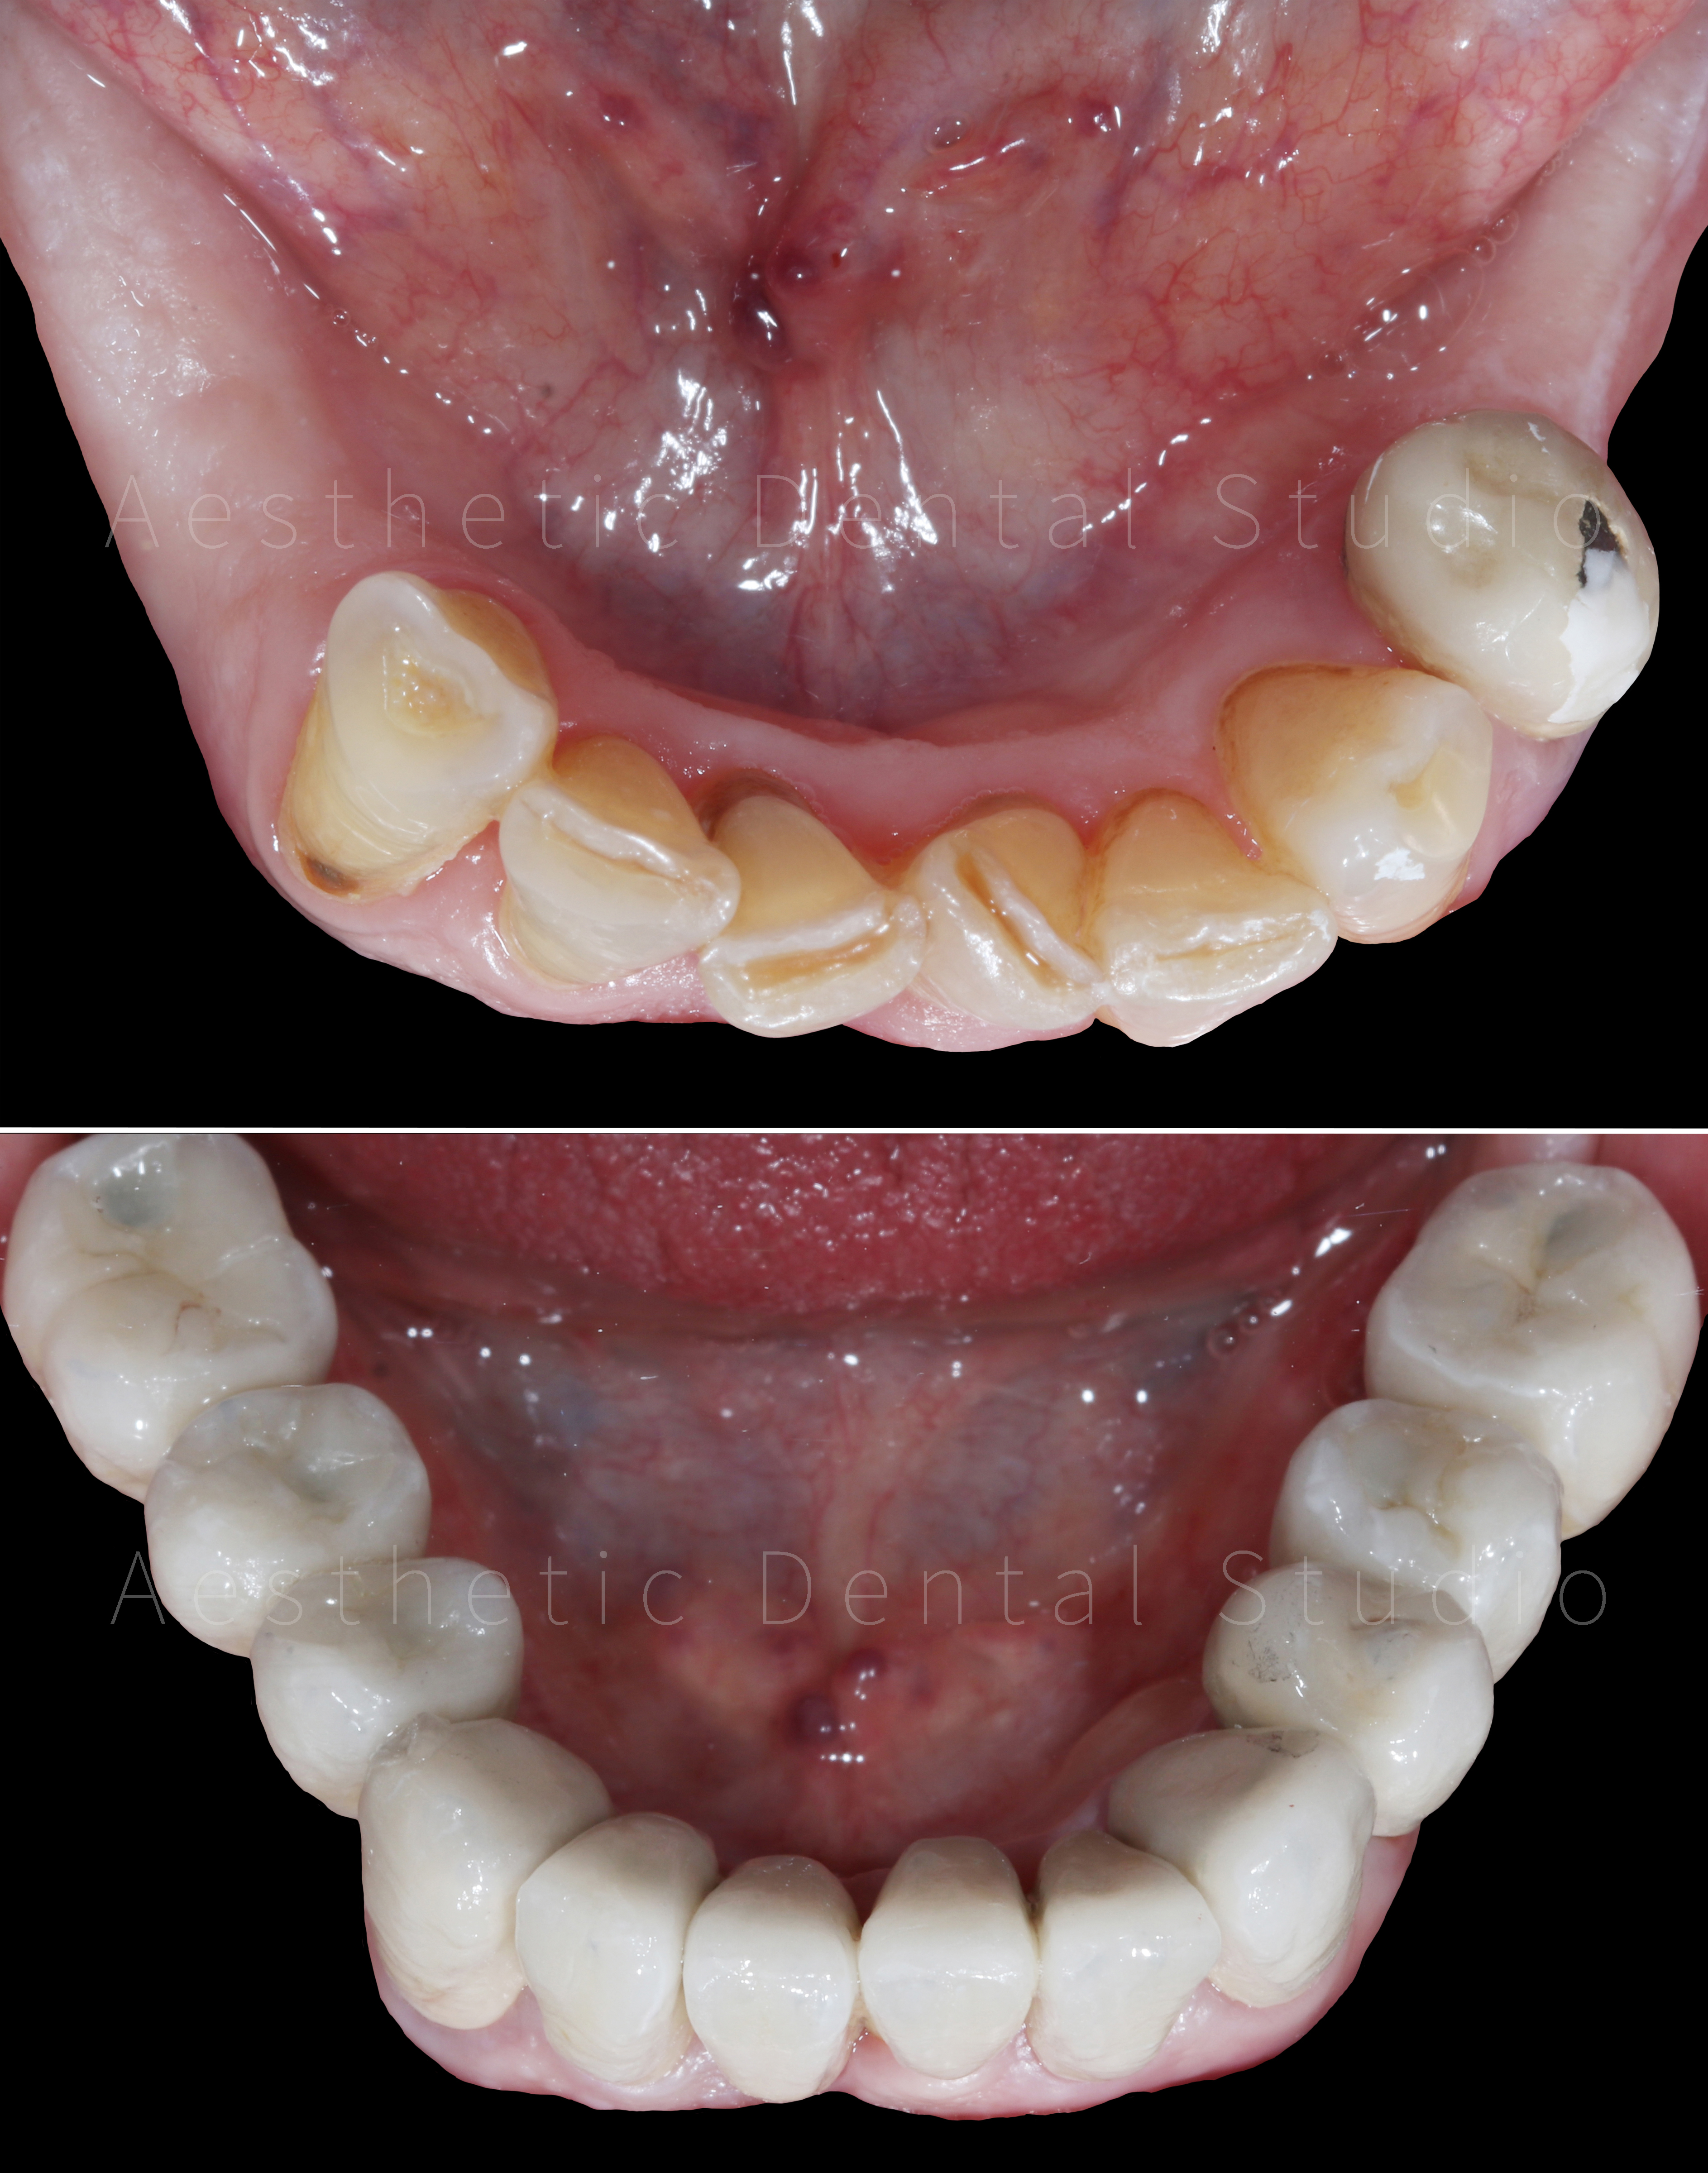

Ασθενής με εκτεταμένη φθορά και απώλεια δοντιών στην άνω και κάτω γνάθο προσήλθε στο Aesthetic Dental Studio στην Καλαμάτα με έντονη δυσκολία στη μάσηση, αισθητικά προβλήματα και επαναλαμβανόμενους πόνους. Η στοματική κατάσταση χαρακτηριζόταν από πολλαπλές τερηδόνες, κατεστραμμένα και ελλείποντα δόντια, γεγονός που επηρέαζε τόσο τη λειτουργία όσο και την αυτοπεποίθηση της ασθενούς.

Στην πρώτη φάση, πραγματοποιήθηκε πλήρης αποκατάσταση της στοματικής υγείας, με αφαίρεση των εναπομείναντων δοντιών της άνω γνάθου, αφού αυτά κρίθηκαν μη αποκαταστάσιμα. Παράλληλα διατηρήθηκαν τα κάτω πρόσθια δόντια και αποφασίστηκε η μετέπειτα προσθετική αποκατάστασή τους. Στην συνέχεια, ακολουθήθηκε χειρουργική τοποθέτηση εμφυτευμάτων σε στρατηγικές θέσεις με πλήρως ψηφιακό πρωτόκολλο:

Αφού ολοκληρώθηκε η δοκιμαστική φάση και επιβεβαιώθηκε η άψογη λειτουργικότητα και αισθητική του σχεδίου, προχωρήσαμε στη λήψη ψηφιακών αποτυπωμάτων με ενδοστοματικό σαρωτή. Με βάση τα δεδομένα αυτά, σχεδιάστηκαν και τοποθετήθηκαν ακίνητες κεραμικές αποκαταστάσεις (στεφάνες και γέφυρες) πάνω σε δόντια και εμφυτεύματα, εξασφαλίζοντας απόλυτη ακρίβεια εφαρμογής και φυσικό αισθητικό αποτέλεσμα.